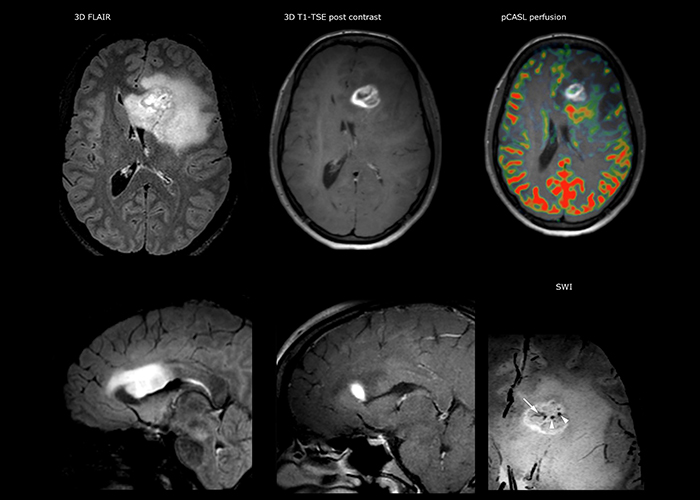

Comprehensive exam answers complex brain tumor questions

Dr. Savatovsky uses five or six different ExamCards for imaging a mass or a known tumor in the brain. “If there is a mass in the brain we try to characterize it to inform the neurologist for determining next steps or to help neurosurgeon prepare for a surgery or biopsy. For follow-up after treatment we have different protocols for different treatments and we adapt for intra- or extra-axial tumors.”

“The biggest challenges are properly characterizing the lesion and giving the surgeon all the information needed, such as the location of vessels and functional areas. Sometimes a very comprehensive exam is necessary, such as when a mass has been discovered at another hospital after which the patient is referred to us. We then do both lesion characterization and preoperative imaging in one exam, so both morphologic and functional assessment. For morphologic assessment we will use pre- and post-contrast T1-weighted imaging, FLAIR to assess infiltration, and diffusion. For functional characterization we will perform perfusion, spectroscopy, and susceptibility weighted imaging to look for micro vessels or micro hemorrhage inside the lesion[4]. For preoperative imaging we perform specific morphologic imaging that is compatible with the navigation system; depending on the location of the tumor, we would do fMRI or DTI.”

“That is the most comprehensive exam we would do. Ingenia has the good spatial resolution and high SNR to provide all this information, and the flexibility to use shorter sequences, so we can do a very comprehensive examination in a limited time.”